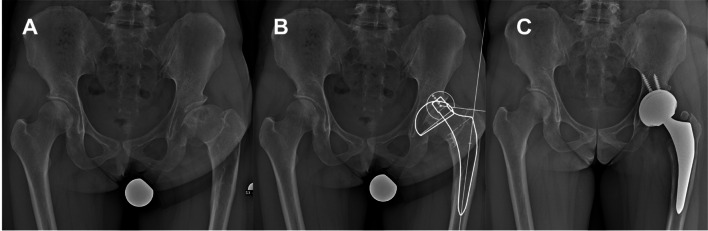

Abstract Image